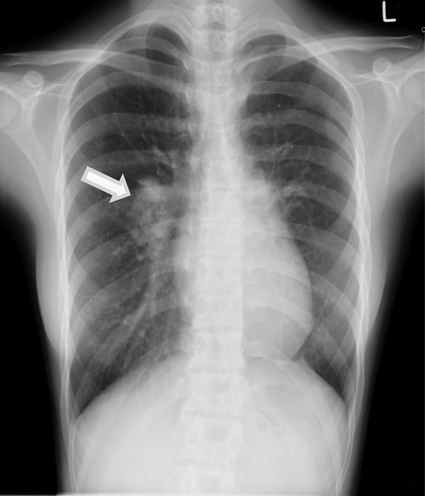

先天性片側肺静脈狭窄に対側のAnomalous Unilateral Single Pulmonary Veinを合併した1例A Case of Congenital Unilateral Pulmonary Vein Stenosis with Contralateral Anomalous Unilateral Single Pulmonary Vein